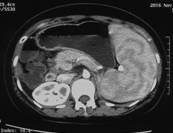

朱××,男,45岁,双侧股骨头坏死,左侧髋关节疼痛明显,不能独立行走,需使用止痛药物(图1,MR)。介入治疗术中造影(图2a)示:股骨头供血动脉分支稀疏,远端痉挛、股骨头骨质内无明显分支动脉血管;治疗后(图2b)造影见股骨头供血动脉分支血管明显增多,远端可见达股骨头骨质内,原髋关节疼痛消失,自行行走出院。

图1 图2a 图2b